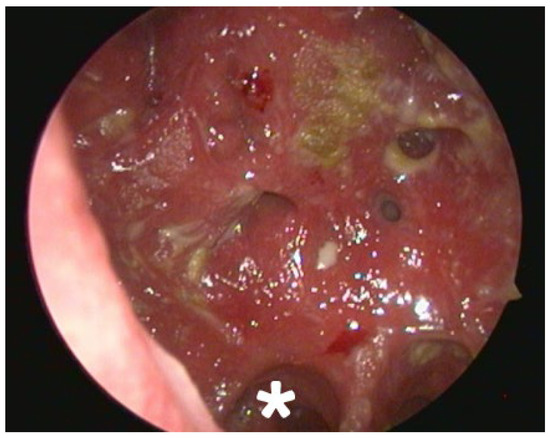

Background and Clinical Significance: Atrophic rhinitis (AR) is a rare, chronic inflammatory condition characterized by progressive atrophy of the nasal mucosa and underlying bone. The present report describes a case of severe secondary AR as a sequela of COVID-19-associated necrotizing rhinitis, highlighting the diagnostic and management challenges posed by multi-drug resistant pathogens and extensive anatomical destruction. Case Presentation: A 75-year-old female developed progressive necrotizing rhinosinusitis with osteomyelitis following a COVID-19 infection. Computed tomography (CT) confirmed an osteolytic process and subsequent profound anatomical destruction, while histopathology ruled out invasive fungal disease. The resulting cavity was colonized by multi-drug resistant Pseudomonas aeruginosa and Staphylococcus aureus. Management and Outcome: Management focused on preventing crust formation through a structured “nasal rest” protocol, supplemented by cleansing nasal douching with a surfactant (baby soap) and mechanical crust removal. This treatment led to significant clinical improvement, with reduced crusting and complete resolution of ozena symptoms. Conclusions: This case illustrates the potential for SARS-CoV-2 infection to precipitate severe necrotizing sinonasal complications leading to secondary AR. It demonstrates the efficacy of a management strategy focused on mechanical cleansing and nasal rest, particularly when conventional antibiotic therapy is limited by extensive drug resistance. Full article

Show Figures

Figure 1